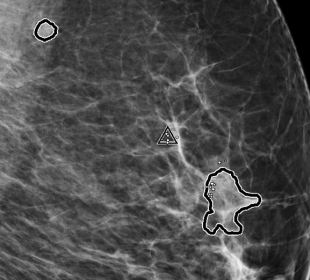

Screening & Diagnosis